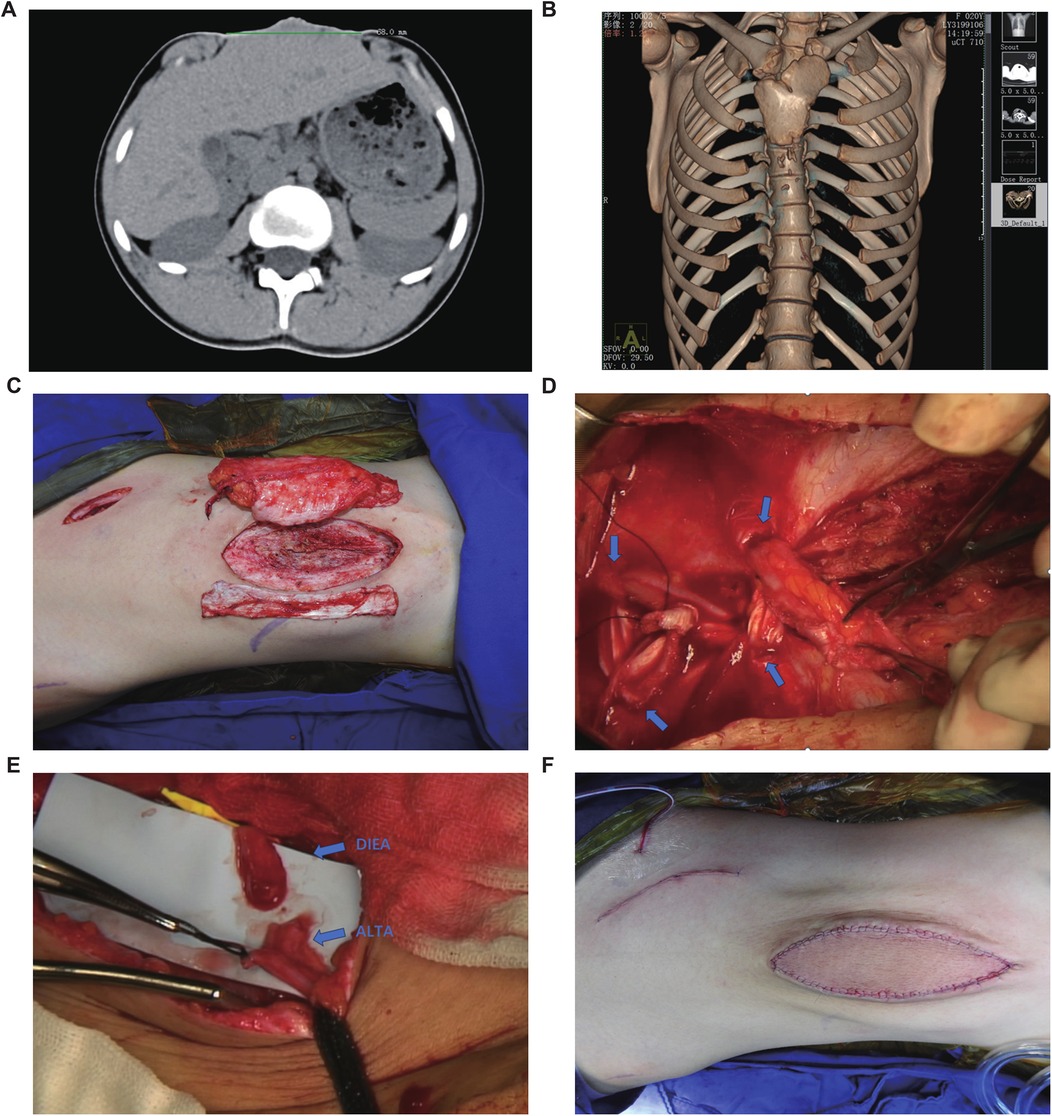

Preoperative non-contrast CT with 3D reconstruction revealed sternal cleft, rib hypoplasia, scoliosis, and diastasis recti (max width 6.8 cm), without organ, cardiopulmonary, diaphragmatic hernia, cardiac malformation, or gastroschisis abnormalities (Figures 2A,B). Following evaluation, congenital omphalocele repair was performed using a left free ALT flap with fascia lata strips. In designing the flap, the following aspects were considered: (1) the abdominal wall structure is similar to that of the lateral thigh, both consisting of a dense fascial layer, an adipose layer, and a cutaneous layer. The fascia lata is anatomically analogous to the abdominal wall fascia. (2) The perforators of the anterolateral thigh vessels have consistent anatomy (as confirmed by ultrasound localization) and a large internal diameter, which relatively reduces the risk of vascular complications. (3) The soft tissue thickness of the abdominal wall and the anterolateral thigh is comparable, minimizing the likelihood of flap bulkiness and potentially avoiding the need for secondary debulking procedures. Regarding the selection of recipient vessels, although the defect was located relatively cranially and the internal thoracic artery and vein could have been feasible options, we ultimately chose the inferior epigastric vascular pedicle for microvascular anastomosis for the following reasons: (1) the internal thoracic artery originates from the subclavian artery and traverses the thoracic cavity to enter the abdominal wall, and its terminal branches contribute to the blood supply of the rectus sheath and abdominal wall. While the diameter of the abdominal segment of the internal thoracic artery is similar to that of the anterolateral thigh artery, utilizing the main trunk of the internal thoracic artery as the nourishing vessel for the flap could potentially compromise blood supply to the ipsilateral abdominal wall postoperatively, particularly considering the increased abdominal wall tension after surgery. (2) The main trunk of the inferior epigastric artery (IEA) has a consistent anatomical location, which is more conducive to preoperative ultrasound localization. Therefore, the ALT flap was selected as the donor site, and the IEA trunk was chosen as the recipient vessel (Figure 2C).

Figure 2. Preoperative examination and surgical procedure. (A) Abdominal CT suggests that the maximum diameter of the abdominal defect is 68 mm. (B) Chest CT scan (non-contrast) with three-dimensional volume rendering reveals asymmetric bilateral clavicles, sternal cleft with associated rib hypoplasia, and scoliosis. (C) The selected autologous free anterolateral thigh flap with fascia lata. (D) The inferior end of the rectus abdominis muscle was interwoven with the fascia lata. The blue arrow indicates the fenestration site in the rectus sheath. (E) The anastomosis site between the perforating branch of the deep inferior epigastric artery (DIEA) and the perforating branch of the anterolateral thigh artery (ALTAP). (F) Postoperative abdominal photograph.

Under general anesthesia in the supine position, a weakened abdominal skin area (∼10 cm × 6 cm) was marked for resection. A left ALT flap (10 cm × 6 cm) with adjacent fascia lata (10 cm × 6 cm) was designed using Doppler-localized perforators. Incision along the flap's lateral border exposed the fascia lata. A dominant intermuscular septal perforator was identified and meticulously dissected retrograde to its source artery with needle-tip electrocautery, ligating branches. The robustly perfused flap was elevated and temporarily secured.

Abdominal skin incision revealed dense peritoneal adhesions. Skin excision exposed the peritoneum. Circumferential subcutaneous dissection (∼5 cm) exposed significantly diastased recti (widest separation ∼5 cm). A preoperative Doppler-guided oblique right lower abdominal incision exposed the right IEA perforator. The main IEA trunk was dissected (∼10 cm to wound), and a subcutaneous tunnel was created.

Returning to the thigh, the ALT flap pedicle was fully exposed, and the anterolateral femoral cutaneous nerve was isolated and transected. After ligating pedicle branches, the flap was elevated with an ∼8 cm pedicle. An additional fascia lata strip (∼10 cm × 4 cm) was harvested. The thigh donor site was closed in layers.

At the abdomen, bilateral anterior rectus sheath perforations were made. The fascia lata strip was anchored to the left rectus, threaded through perforations, tensioned to reduce diastasis by ∼2.5 cm, and secured (Figure 2D). The upper recti were temporarily approximated, reducing diastasis to 2.5 cm. It is important to note that the significant volume of abdominal contents and the resulting high wall tension preclude primary complete approximation of the rectus abdominis muscles, as this would lead to vascular compromise. The ALT flap with attached fascia was transferred; its fascia lata was overlapped bilaterally (∼2 cm) onto the upper diastasis and sutured to the anterior sheath. Removal of temporary sutures confirmed uniform tension before flap inset (Figure 3).

The vascular pedicle was transposed through the tunnel to the IEA trunk. After distal ligation and proximal division, end-to-end microanastomosis (artery and veins) to the IEA trunk was performed under microscopy using 9–0 sutures (Figure 2E). Upon clamp release, robust perfusion was confirmed. Abdominal closure was completed with layered sutures, and closed-suction drains were placed.